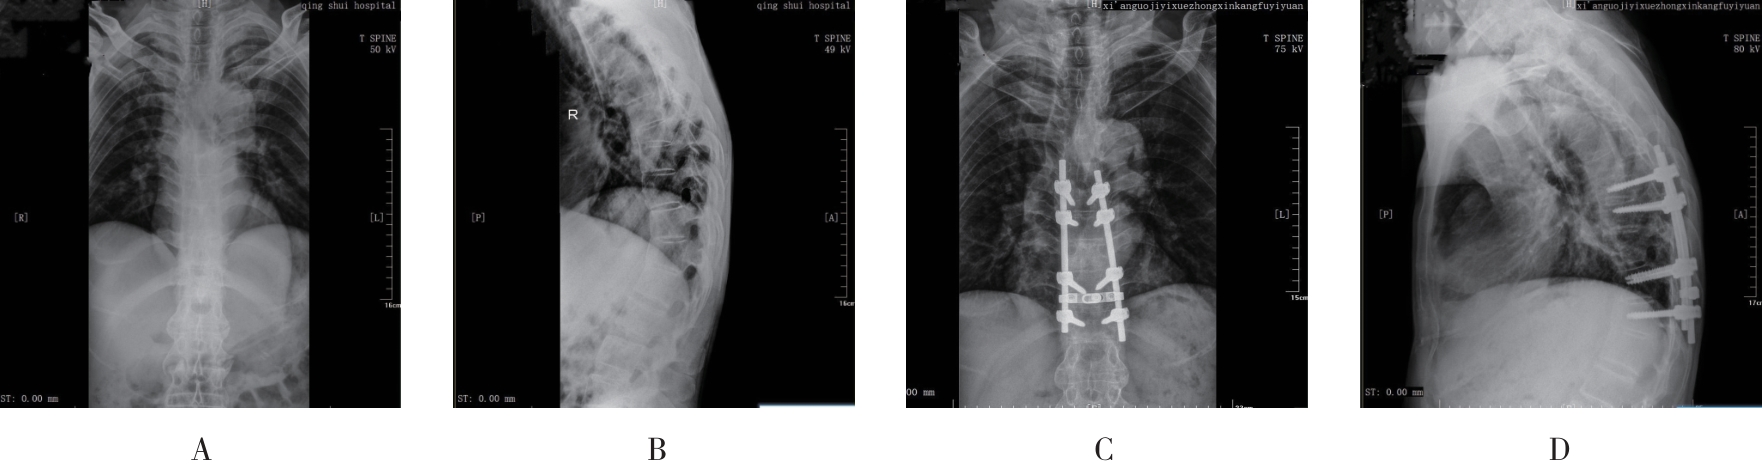

• 3D个体化打印导向器在强直性脊柱炎胸腰椎骨折中的应用

2025, 35(20):89-95. DOI: 10.3969/j.issn.1005-8982.2025.20.015

摘要 (124) HTML (53) PDF 1018.03 K (65) 评论 (0) 收藏

摘要:目的 评估3D个体化打印椎弓根螺钉导向置入在强直性脊柱炎患者胸腰椎骨折中的应用效果。方法 回顾性选取2019年1月—2022年10月在西南医科大学附属医院治疗的104例强直性脊柱炎合并胸腰椎骨折患者的临床资料。根据不同置钉方式分为观察组和对照组,分别有53、51例。观察组进行3D打印椎弓根导板辅助置钉;对照组采用传统X射线辅助徒手置钉。比较两组患者围手术期指标、术后1 d的应激指标[血清促肾上腺皮质激素(ACTH)、皮质醇(Cor)],并对比术前和术后12个月的视觉模拟评分法(VAS)、日本骨科协会腰椎功能评分(JOA)、骨代谢指标[骨钙素、骨碱性磷酸酶(BALP)]、脊柱三维运动范围、伤椎Cobb角、伤椎前缘高度和后缘高度。结果 观察组手术时间、置钉时间、切口长度短于对照组(P <0.05),术中出血量低于对照组(P <0.05),螺钉调整次数少于对照组(P <0.05)。观察组术后1 d ACTH、Cor水平均低于对照组(P <0.05)。观察组手术前后ACTH、Cor的差值均低于观察组(P <0.05)。观察组术后12个月VAS评分均低于对照组(P <0.05),JOA评分、骨钙素、BALP均高于对照组(P <0.05)。观察组患者手术前后VAS评分、JOA评分、骨钙素、BALP的差值均高于观察组(P <0.05)。观察组术后12个月脊柱前屈、后伸、侧屈和旋转范围均大于对照组(P <0.05)。观察组手术前后脊柱前屈、后伸、侧屈和旋转范围的差值均高于观察组(P <0.05)。观察组术后12个月的伤椎前缘高度、后缘高度均高于对照组(P <0.05),伤椎Cobb角低于对照组(P <0.05)。观察组手术前后伤椎Cobb角、伤椎前缘高度和后缘高度的差值均高于观察组(P <0.05)。结论 3D个体化打印导向器引导的椎弓根置入有助于强直性脊柱炎患者胸腰椎骨折后的恢复。